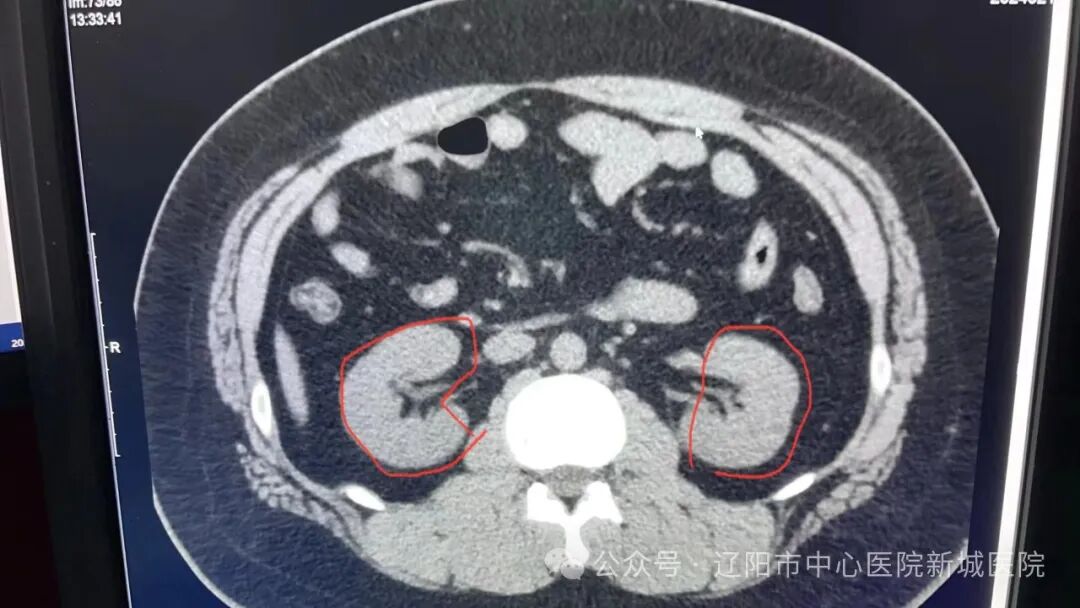

2月5日,已臨近春節(jié),新城醫(yī)院泌尿外科收治了一位中年男性患者,病因是他在家里整理重物時,突然感到腰部劇痛,肢體不能活動。CT檢查提示:腰椎陳舊性骨折,左腎區(qū)巨大占位15cm×13cm,患者緊急辦理了入院手續(xù)。

正常腎臟圖片

病患腎臟圖片